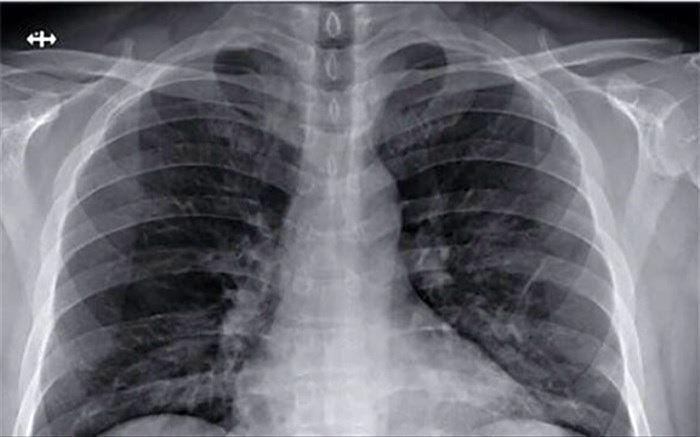

تهران (پانا) - اگر تا به حال یک نخ سیگار هم نکشیدهاید شاید تصور کنید در برابر سرطان ریه مصون هستید؛ اما طبق آمار اخیر، اشتباه میکنید. هرچند کشیدن سیگار، اولین ریسک فاکتور ابتلا به سرطان ریه است؛ اما پژوهشهای جدید نشان میدهند نرخ سرطان ریه در افرادی که هرگز سیگار نکشیدهاند، یک روند افزایشی پیوسته پیدا کرده است.

تهران (پانا) - یک فوق تخصص ریه دانشگاه علوم پزشکی کاشان گفت: بیماری ناشی از ویروس کرونا در ابتدا یک بیماری تنفسی است که با توجه به حجم ویروس حمله کننده و پاسخ ایمنی فرد مبتلا می تواند به راههای هوایی فوقانی مثل بینی و گلو محدود شود و یا پیشرفت کرده و مجاری تنفسی تحتانی و بافت ریه را نیز درگیر کند.

تهران (پانا) - کروناویروس بهخاطر وجود شاخکهای تاجی شکلی که بر روی سطوحش وجود دارد، با این نام شناخته شده و میتواند سبب بروز کووید 19 شود. این ویروس یک عفونت ویروسی واگیردار است که در ابتدا گلو و سپس ریه فرد مبتلا را درگیر میکند.